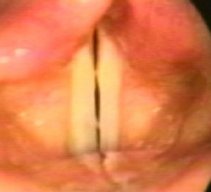

両側に結節あり |

2.

発声時にスキマがある |